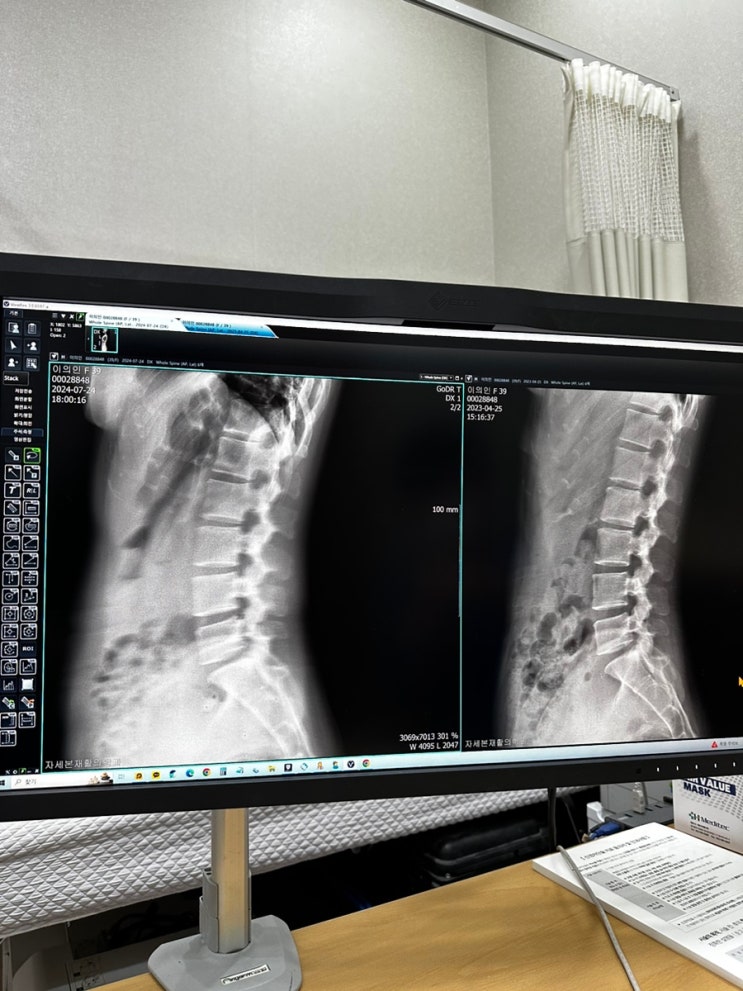

상왕십리역 자세본재활의학과 허리 통증으로 방문했어요

안녕하세요:) 이아나입니다 지난주에 신나게 운동하고 러닝하고 왜 허리가 아프죠??? 에이 하루 이틀 있으...